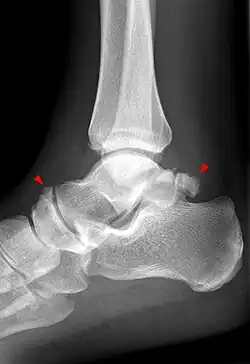

Beim Röntgen ist das Os trigonum als dreieckiges, rundes oder ovales Gebilde am Processus posterior tali bei seitlicher Aufnahme am besten zu erkennen. In den meisten Fällen ist es ein einzelner Knochen, es können aber auch mehrere Os trigonum ausgebildet sein.